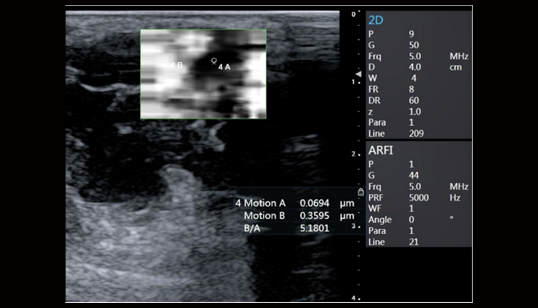

Acoustic Radiation Force Imaging: 声辐射力弹性成像(ARFI)

基于声能 (ARFI)和剪切波波速的实时弹性成像,提供组织软、硬病变的定量评价。 通过自动发射一定能量的声波通过声辐射力直接对所需要检测部位进行激励,用 于激励的声波犹如无形的手直接去推动组织产生运动,从而得到表征组织弹性的图像,这种新兴弹性成像技术可以得到更精确的组织应变图像

shear wave imaging:剪切波成像技术(SWI)

基于ARFI技术衍生的超声剪切波成像,通过调整脉冲激励方式,根据水平方向多个点的位移-时间曲线估算横向传播的剪切波波速,然后利用剪切波传播特性与生物组织弹性特征之间的内在联系,最终定量重构组织的弹性模量以形成二维的图像。